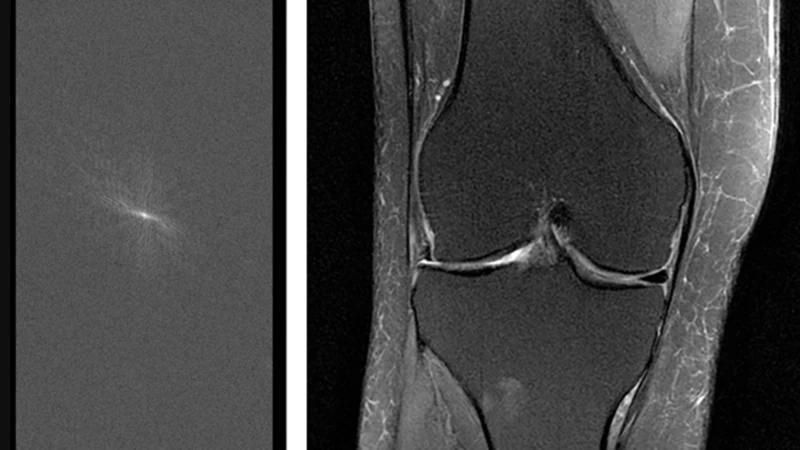

ジーナ・シアヴァラは、マンハッタンにあるニューヨーク大学ランゴン・ヘルスの暗い部屋に座っている。そこは読影室で、彼女のような放射線科医がX線やMRIのスキャン画像を検査する場所だ。目の前のモニターには、匿名化された患者の膝のグレースケール画像が映し出されており、彼女はそこに一つの重大な問題を発見した。前十字靭帯(ACL)断裂だ。「これは間違いなく異常です」とシアヴァラは説明する。

しかし、シアヴァラには、骨、靭帯、脂肪、軟骨、腱の渦巻きをスキャンして断裂や関節炎などの問題がないか確認するだけでなく、もう一つ評価しなければならないことがある。この膝のスキャン画像は人工知能(AI)によって作成されたものだろうか、それとも従来のMRI装置から生成されたものだろうか?「直感的にAIだと思います」と彼女は確信を持てずに言う。「ただ、少しぼやけているように見えるだけです」

Facebookはモデルを開発した後、鋭い観察眼を持つ専門家によるブラインドテストを実施する必要がありました。シアバラ氏をはじめとするニューヨーク大学の放射線科医たちは、AIによって生成された膝のスキャン画像と従来の方法で作成された膝のスキャン画像を検証し、両方から同じ診断情報が得られるかどうかを検証しました。そして、どちらが正しいかを推測する必要がありました。患者を2回スキャンする(つまり、より遅い通常の方法と、より高速なAIを活用した方法)のではなく、チームは通常のスキャン画像から生データの一部を遡及的に抽出し、機械をより高速に動作させた場合の状況をシミュレートしました。

ジトニック氏はまた、AIが生成した画像に少しノイズを加えてよりリアルに見せ、医師に情報が漏れるのを防いだと指摘する。「ちょうどいい具合に調整すると、放射線科医はどれがAIによるものでどれがそうでないかを見分けるのが非常に難しくなります。なぜなら、そこにあったたった一つのヒントが消えてしまうからです」と彼は言う。(追加されたノイズはスキャンの診断価値に影響を与えなかったと彼は言う。)